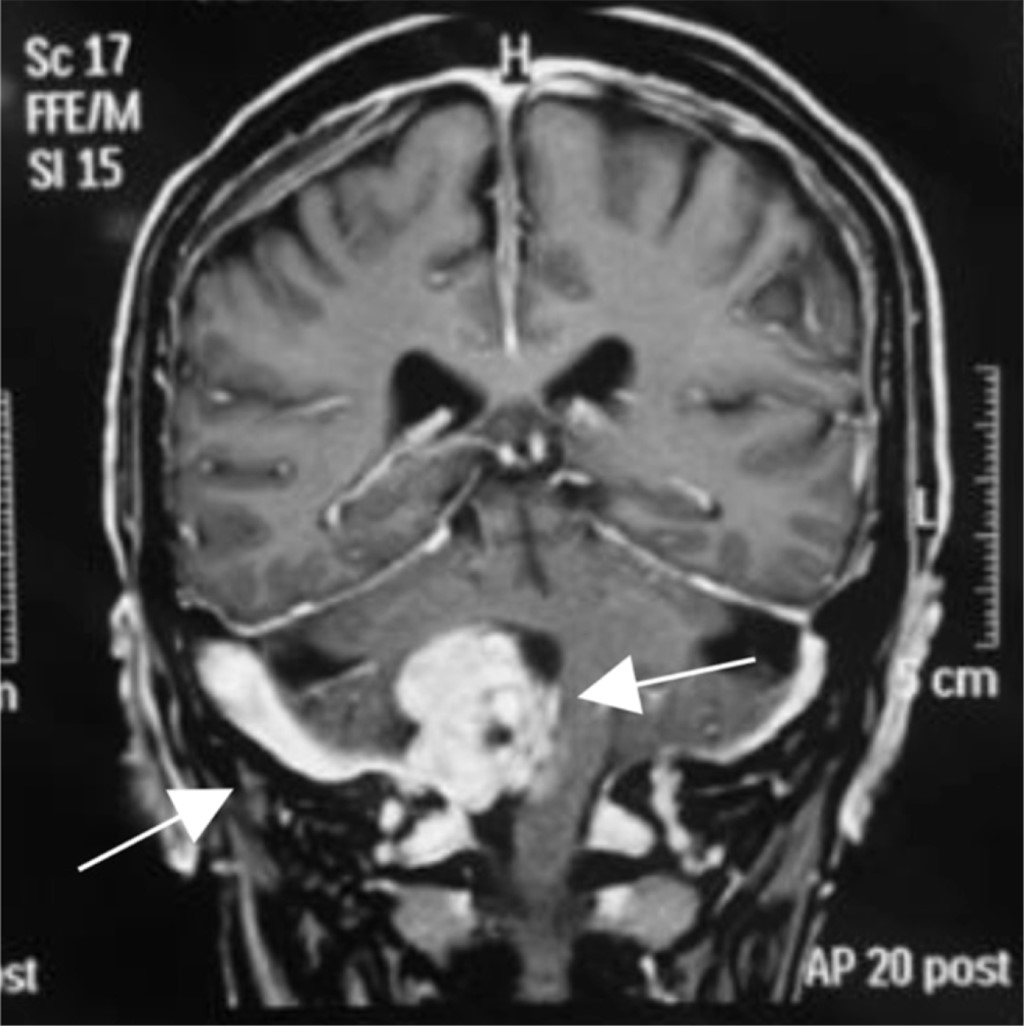

Figure 1